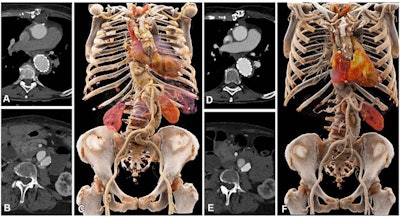

First author Dr. Kai Higashigaito, also of the University Hospital Zurich, and colleagues conducted a study that explored use of a low-volume contrast media protocol with PCCT for CCTA of the aorta in the chest and abdomen. The research included 100 people, all of whom had undergone CCTA with conventional CT and all of whom underwent CCTA with PCCT. The study participants were divided into two groups: 40 people who underwent imaging between April and May 2021, and 60 who underwent imaging between June and September 2021.

Among the first group, the team found that PCCT conducted at 50 keV offered "the best trade-off between objective and subjective image quality," reaching a 25% higher contrast-to-noise ratio compared with conventional CT. In the second group, contrast media volume was reduced by 25%.

"CCTA of the aorta with [PCCT] was associated with higher contrast-to-noise ratio, which ... translated into a low-volume contrast media protocol demonstrating noninferior image quality compared with [conventional] CT at the same radiation dose," the authors concluded.